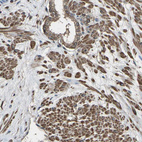

Immunohistochemical staining of human testis shows moderate to strong cytoplasmic positivity in cells in seminiferous ducts.